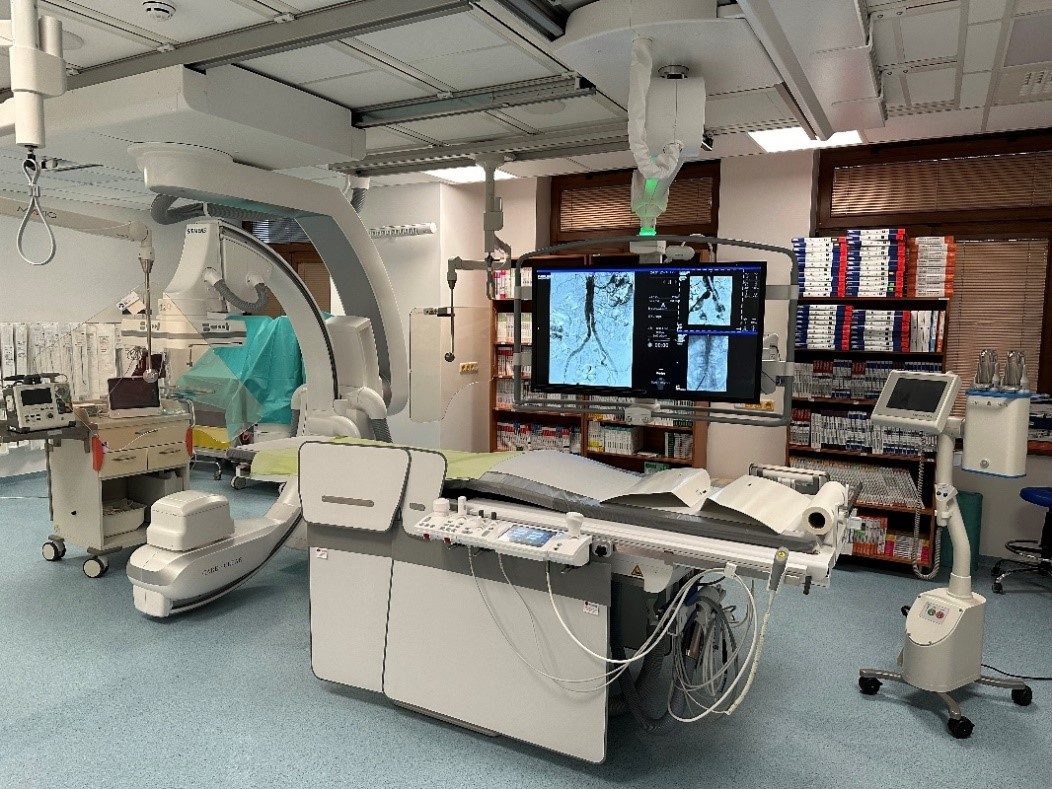

V Stredoslovenskom ústave srdcových a cievnych chorôb a.s. pomôže pacientom s cievnymi ochoreniami nový angiografický systém ARTIS Q od spoločnosti Siemens Healthineers. Prístroj, ktorý nahradil už zastaralý systém staršej generácie, je určený na diagnostiku a liečbu ochorení ciev v celom anatomickom rozsahu s výnimkou ciev srdca. Nachádza sa v nových, moderných priestoroch pracoviska intervenčnej rádiológie a bude slúžiť hlavne pacientom s aterosklerotickým postihnutím (upchávaním) ciev, výduťami ciev, pacientom s cukrovkou, u ktorých hrozí amputácia končatiny, ďalej pacientom s rozsiahlou hlbokou žilovou trombózou a pľúcnou embóliou.

Choroby ciev postihujú veľkú časť obyvateľstva a predpokladá sa, že ich výskyt bude v nasledujúcich rokoch výrazne stúpať. Nový angiograf vďaka špičkovej technológii skráti čas vyšetrenia pacienta, výrazne zredukuje radiačnú dávku a aj objem podanej kontrastnej látky pri zachovanej najvyššej kvalite zobrazenia. Okrem plánovaných zákrokov zaisťuje pracovisko intervenčnej rádiológie aj nepretržitú 24 hodinovú príslužbu pre akútne neodkladné stavy.

Slávnostné otvorenie tohto nového intervenčného pracoviska bolo dňa 2.2.2024 aj za účasti pani ministerky zdravotníctva Zuzany Dolinkovej.